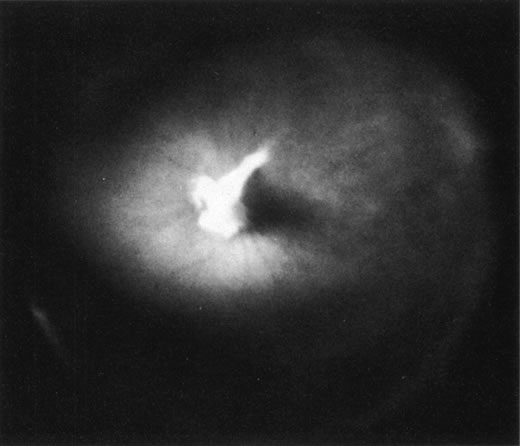

The retina is usually not involved in anterior PHPV. Indeed, previous studies have suggested that the anterior form is due to a primary defect in lens development and that vitreous changes are all secondary.34 This postulate has never been substantiated. There are rare instances of posterior PHPV in which opaque connective tissue arises from Bergmeister's papilla and persistent hyaloid vessels (Fig. 1).32,35 These can cause congenital falciform folds of the retina and, if severe, can cause tentlike retinal folds, leading on rare occasions to tractional and/or rhegmatogenous retinal detachment. Font and investigators36 demonstrated the presence of adipose tissue, smooth muscle, and cartilage within the retrolental plaque and suggested that PHPV arises from metaplasia of mesenchymal elements in the primary vitreous.

Fig. 1. Persistent hyperplastic primary vitreous (PHPV). A wide-angle fundus photograph of the left eye in a 10-year-old boy with the posterior form of PHPV demonstrates a fibrous stalk arising from the optic disc and extending into the central vitreous. (Sebag J: The Vitreous: Structure, Function and Pathobiology, p 99. New York, Springer-Verlag, 1989.)